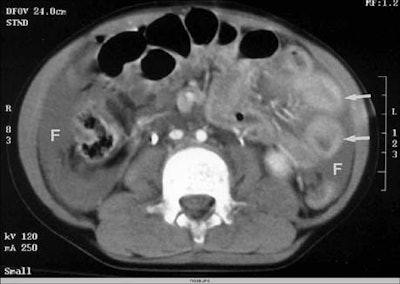

According to the results, CT identified free fluid or organ injury in 112 of 206 patients (54%). The most frequently injured organs were the spleen (39%), liver (30%), kidney (8%), mesenteric bowel (8%), bladder (4%), and the pancreas (3%).

However, for visceral injury without free fluid, ultrasound was only 41% sensitive and 92% specific on the first pass. By the second exam, sensitivity had risen to 51% and specificity to 100%. A quarter of the organ injuries seen on CT did not have free fluid; therefore the first ultrasound missed 73% of these parenchymal injuries, Poletti said.